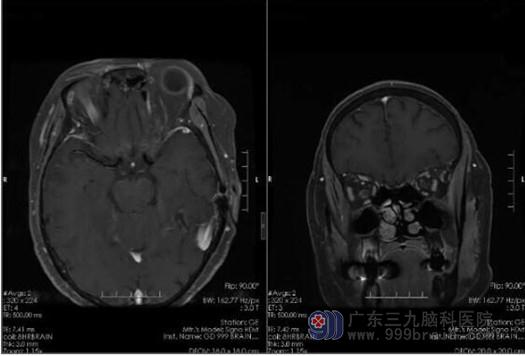

钟阿姨已经有62岁了,从今年2月份开始出现双眼视力下降,伴眼睛疼痛,到当地眼科医院就诊,查双眼视力差,APQ4(-),MOG弱阳性(1:640),头颅MR示视神经增粗,信号异常并强化阿明显,考虑炎性可能性大,诊断为“视神经炎”。予以激素冲击、营养神经、改善微循环等对症治疗后,视力较前好转。但是出院停用一段时间药物后,钟阿姨再次出现视力下降。为进一步诊治,钟阿姨来到三九脑科医院做进一步治疗。

入院查体示双眼视力减退,以右眼视力下降显著,左眼、双眼Snellen视力6/60,右眼指数,余无阳性病理征。主管医生叶锦龙医生结合钟阿姨的症状、体征、外院资料等,考虑视神经脊髓炎谱系疾病(NMOSD)可能性大。

在确定诊断方向后,一方面予以病因治疗,另一方面我科继续完善相关检查。住院期间复查MOG抗体:阳性(1:32),3.0TMR眼眶平扫结果显示:右侧视神经束膜呈轻度强化。